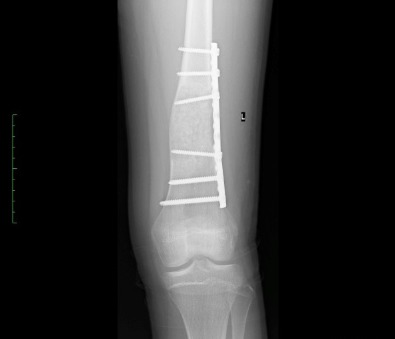

Νόσος του Όλιερ

Οι εικόνες απεικονίζουν ένα περιστατικό με την Νόσο του Όλιερ, όπου παρουσίαζε κοντύτερο αριστερό άκρο. Χειρουργήθηκε από τον Δρ. Ζένιο με την χρήση εξωτερικής οστεοσύνθεσης.

Προ-εγχειρητικά

Εξωτερική

οστεοσύνθεση

Μετ-εγχειρητικά